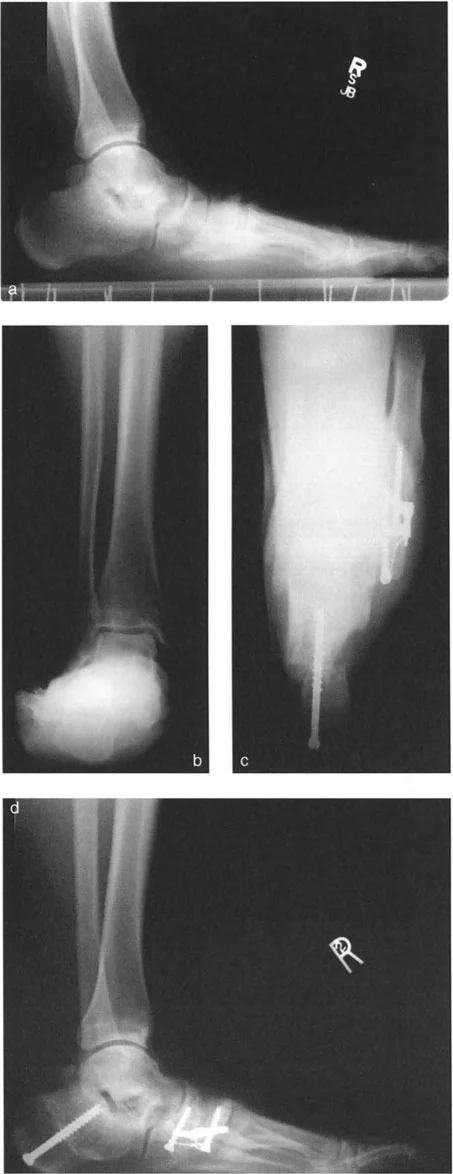

* الأشعة السينية الجانبية والامامية الخلفية للكاحل: تُظهر هذه الصور تفاصيل مفصل الكاحل نفسه، بما في ذلك زاوية القصبة الأمامية البعيدة (ADTA) وزاوية القصبة الوحشية البعيدة (LDTA)، وهي زوايا حاسمة لتحديد التشوه في المستويين الأمامي والسهمي.

* منظر سولتزمان (Saltzman View): هذا المنظر الإشعاعي الخاص يتم الحصول عليه بزاوية 20 درجة لقياس محاذاة عظم العقب (Calcaneus) بالنسبة لقصبة الساق، وهو أمر بالغ الأهمية لتقييم تعويضات القدم الخلفية.

* التصوير المقطعي المحوسب (CT Scan): قد يكون ضروريًا في الحالات المعقدة أو لتحديد تفاصيل الكسور القديمة أو التشوهات ثلاثية الأبعاد، خاصة عند التخطيط الجراحي الدقيق.